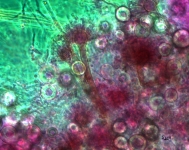

| Species Name: | Aspergillus spinulosporus |

| Taxonomy: | FUNGI Ascomycota, Eurotiomycetes, Eurotiales, Aspergillaceae |

| Characters: | CULTURE CONDITIONS heavy ascomata on PDA - // HUMAN/ ANIMAL PATHOGEN cerebral aspergillosis in a small bowel transplant patient - // MOLECULAR SYSTEMATICS calmodulin sequence has 99% identity to 5 strains of E. echinulata in the GenBank - fide P. Iwen (Click for publications citing UAMH 10948) |